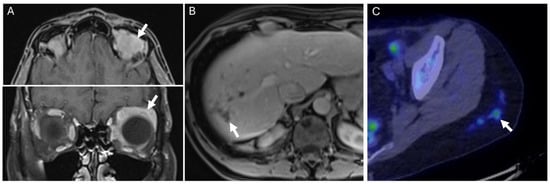

3.2. AL Amyloidosis

| AL Amyloidosis |